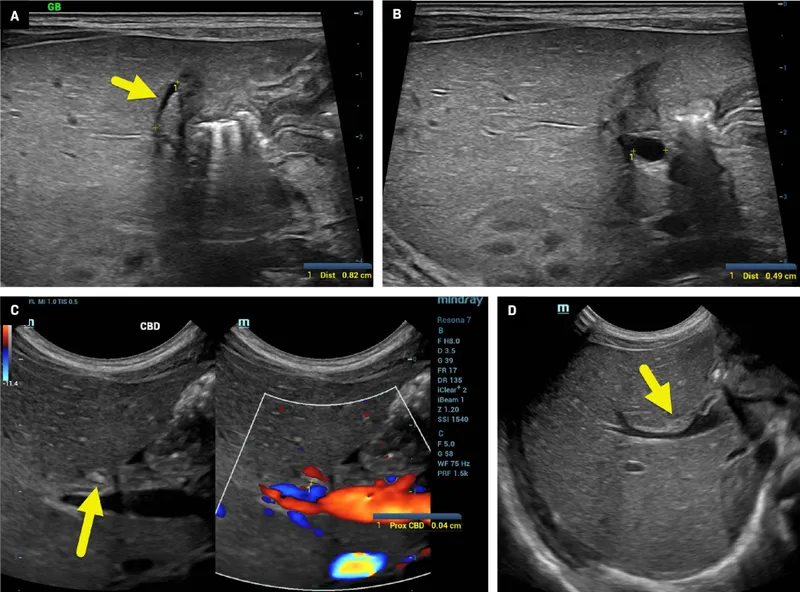

- Intraoperative cholangiogram is diagnostic; triangular cord sign on US is suggestive.